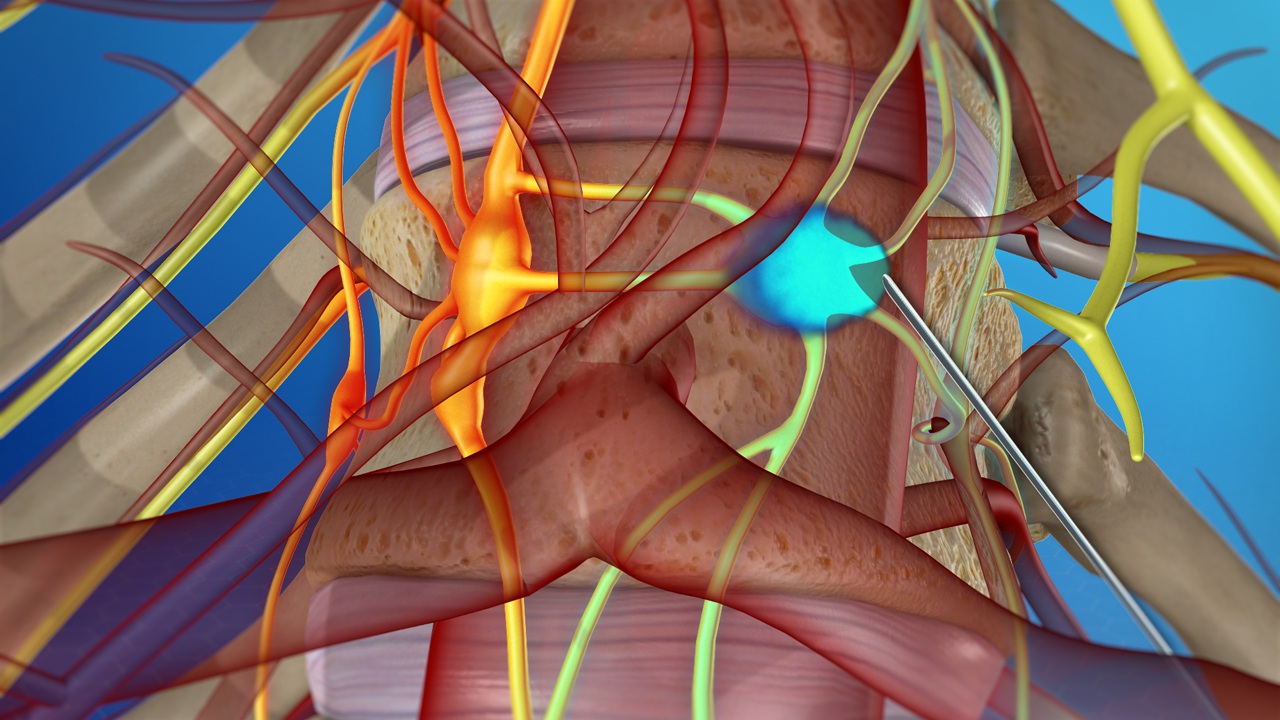

Coeliac Plexus Block

The coeliac plexus is a bundle of nerves in the upper abdomen that transmits many of the pain signals from the organs of the abdomen to the brain. The plexus can be temporarily blocked using local anaesthetics or permanently ablated using phenol or alcohol solutions. Blocking of this plexus is undertaken to relieve sever chronic pain. The block is particularly effective for pancreatic pain such as that of pancreatic cancer or acute and chronic pancreatitis as well as other pains of the upper abdomen.

A coeliac plexus block is performed in the radiology suite using either fluoroscopy or a CT scan. This procedure is undertaken on an in-patient basis and does require hospitalisation.